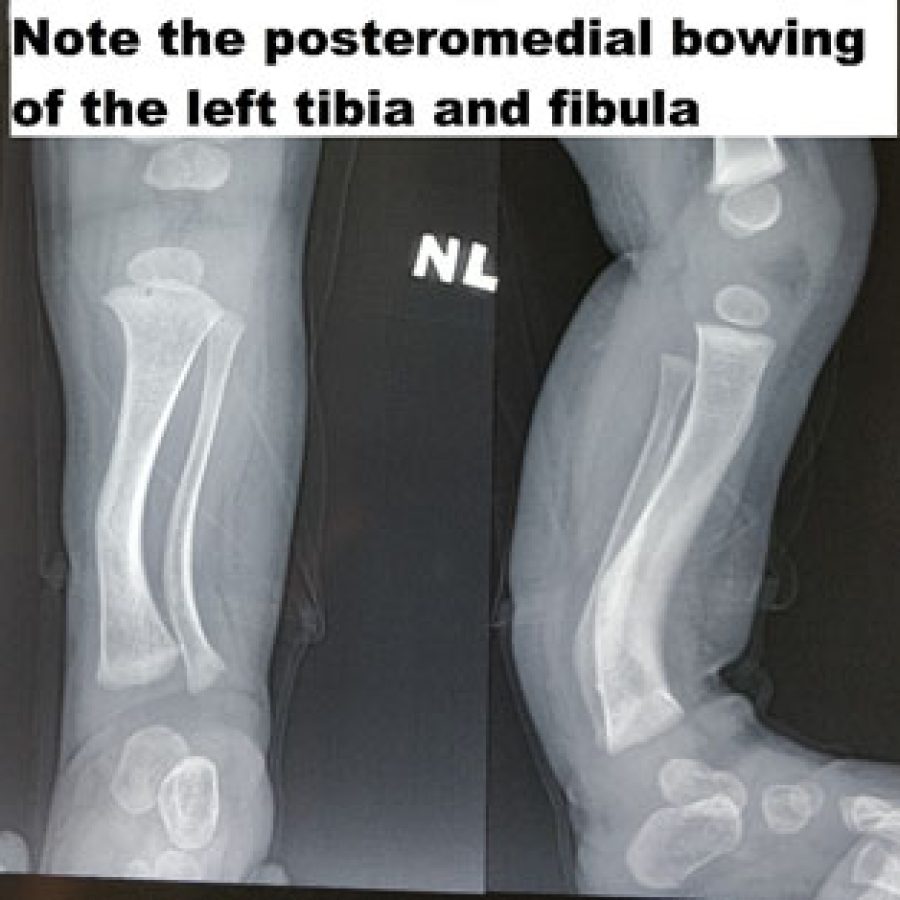

CONGENITAL POSTEROMEDIAL BOWING

Posteromedial bowing is a benign clinical condition with a good natural history. It is mostly due to the intrauterine positioning of the leg. It is most often associated with calcaneovalgus foot. It spontaneously corrects by the age of 5-7 years. If there is more than 3-4 cm of shortening, then surgical intervention is necessary to equalize the limb length.

Most often than not, this should not be confused with anterolateral bowing of the leg, which is almost always pathological. Anterolateral bowing is mostly because of congenital pseudarthrosis of the tibia. Congenital Pseudarthrosis of tibia and fibula is one of the most challenging surgical problems in pediatric orthopedic surgery, and it is important to distinguish from benign posteromedial bowing of the tibia.

When to Refer

It is important to refer all bowing of the leg to the pediatric orthopedic surgeon as sometimes it is difficult to differentiate the two disorders. If one is very sure about the Posteromedial bowing of the leg, then one can wait for 2-3 years with reassurance to the family